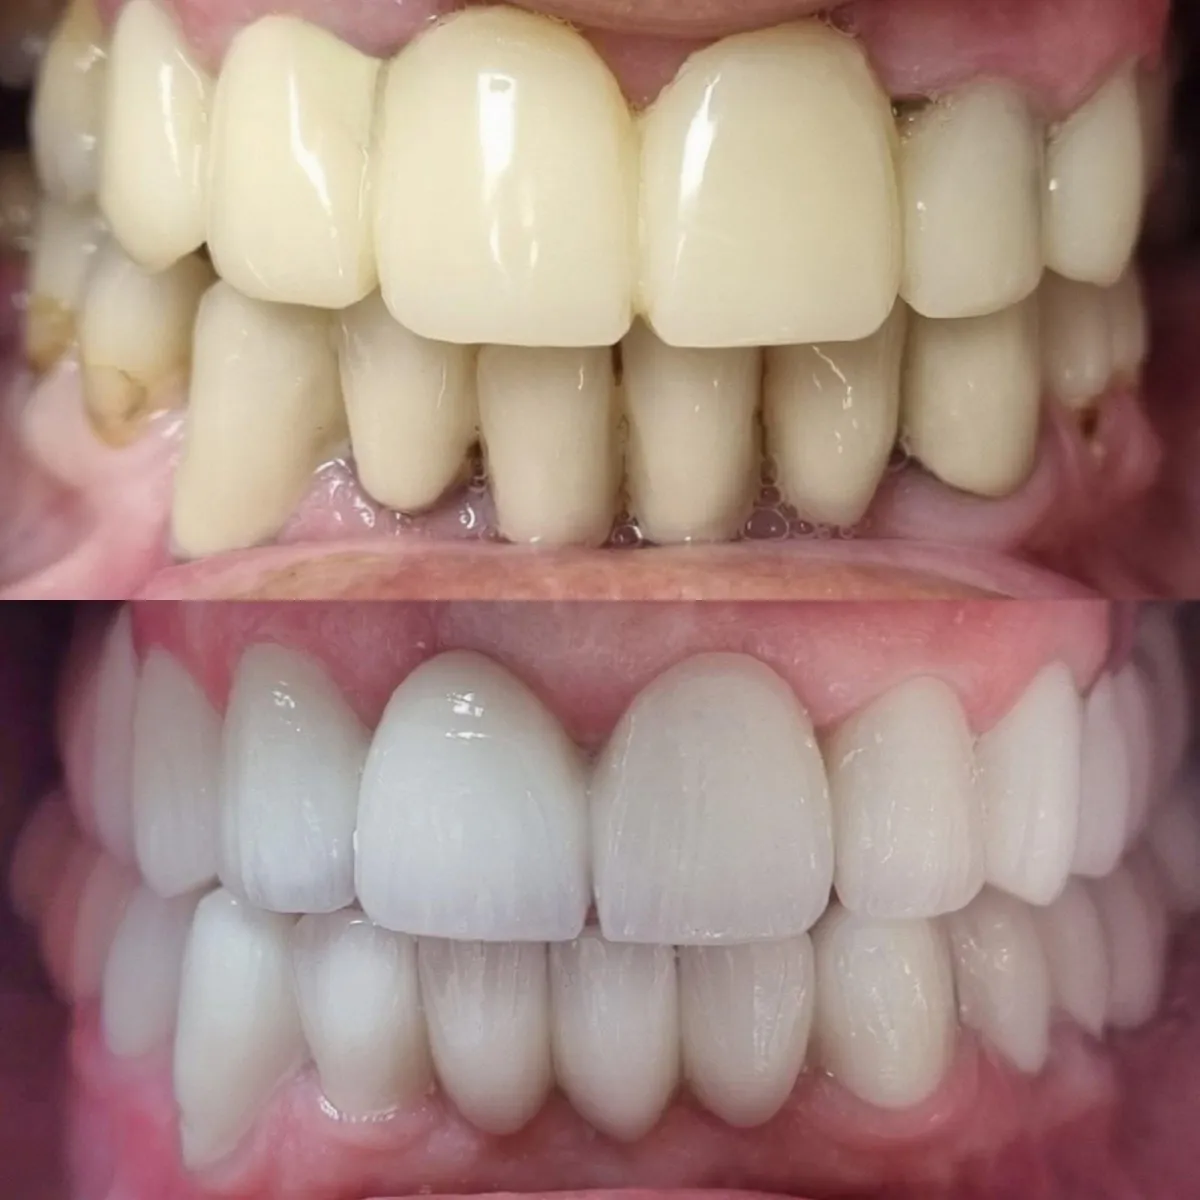

Pogledajte našu galeriju istaknutih radova u Dental Studio dr. Jusić. S ponosom vam predstavljamo rezultate našeg truda, stručnosti i posvećenosti. Bilo da se radi o estetskim zahvatima, implantatima ili ortodontskim tretmanima, naši zadovoljni pacijenti su najbolji dokaz kvalitete naših usluga.